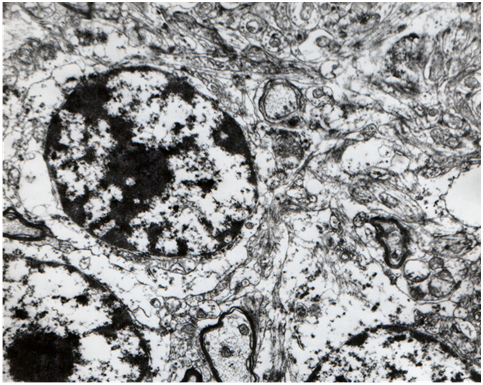

There are four kinds of inhibitory neurons in the cerebellar cortex. The basket cells, the stellate neurons and the Golgi II neurons that produce inhibitory synapses with Purkinje cells using mainly GABA. GABAenergic vesicles are ellipsoid in contrast to the cholinergic which are spheroid. This why Gray named the cholinergic, vesicles S whereas the GABAenergic, vesicles E. The fourth kind of inhibitory neurons are the Purkinje cells which inhibit the cells of the dentate nucleus. We must mention that both basket cells and stellate cells become excited by the parallel fibers whereas the Golgi II cells by the mossy (Figure 1).

Figure 1Stellate cell from the molecular layer of the human cerebellum (48.400x)